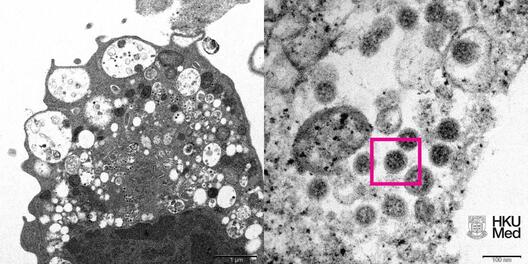

Апублікавана першая выява каронавіруснага штаму «Амікрон». Фотаздымак быў атрыманы з дапамогай электроннай мікраскапіі.

Фота культуры клетак Vero E6 ныркі малпы, заражанай «Амікронам», было зроблена ва Універсітэце Ганконга.

Цёмныя шарападобныя структуры на малюнку — гэта вялікая колькасць каронавіруса штаму «Амікрон».